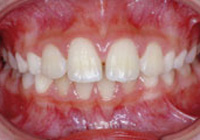

症例1:乱ぐい歯「歯並びが乱れている」

治療前